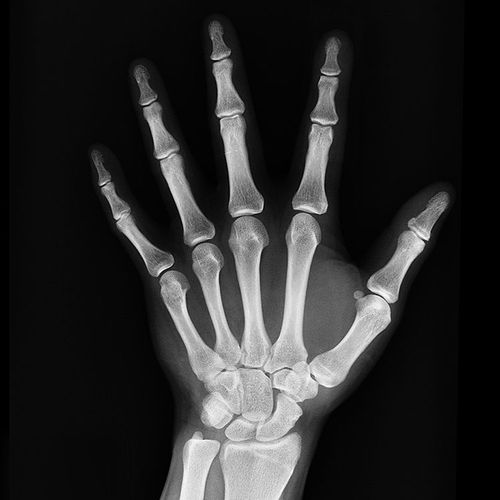

Findings: In the highest quartile, vitamin D supplementation averaged 800 IU (and ranged from 792 IU to 2,000 IU) per day. People in this quartile were 30% less likely to break a hip and 14% less likely to suffer a nonvertebral fracture, such as in a wrist or forearm, than people in all of the other quartiles. In fact, the results showed no benefit in terms of fracture prevention from taking less than 800 IU daily.